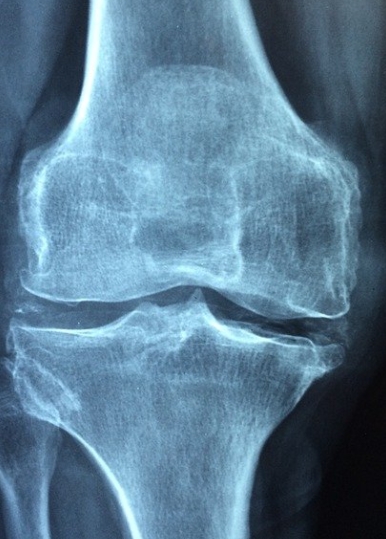

> 관절보호에 좋습니다

연골의 성분으로, 연골 간의 충돌을 예방하고 완화하는 데 중요한 역할을 하는 필수 성분 중 하나로 관절을 안전하게 보호하고 관절 통증을 완화시키는데 도움을 줍니다.

> 연골마모감소에 좋습니다

노화로 인해 연골이 감소하여 뼈와 뼈의 접촉이 더 단단해지면 통증과 염증을 유발합니다. 콘드로이친은 연골성분으로 연골의 마모를 늦춰주면서 관절 통증을 완화시키는데 도움을 줍니다.